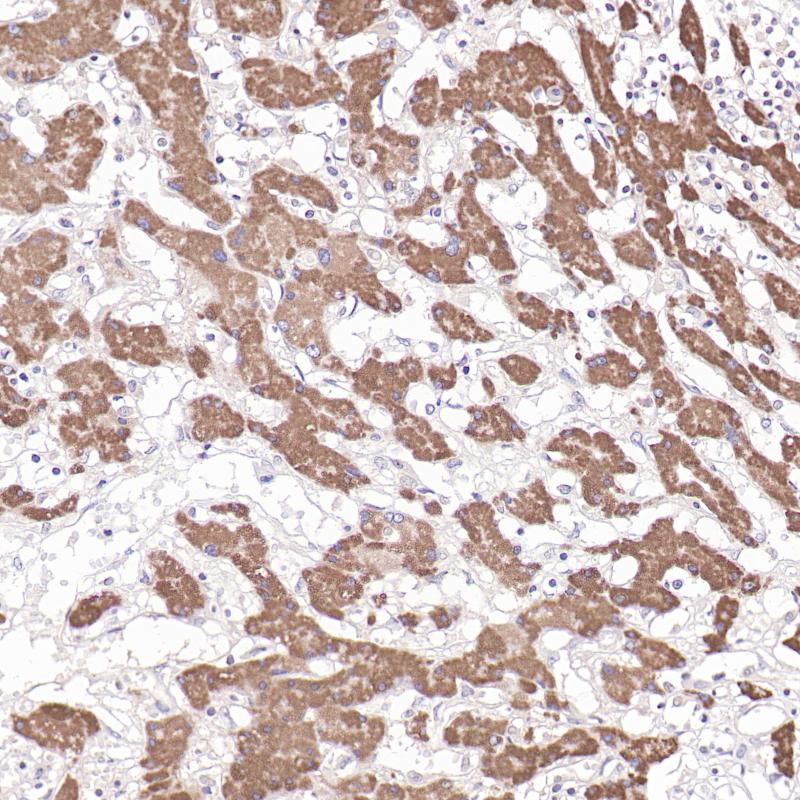

Helicobacter pylori 重组兔单克隆抗体

幽门螺杆菌(Helicobacter pylori, HP)感染是导致慢性胃炎、消化性溃疡以及胃癌的重要病因。在临床诊断中,可通过免疫组织化学方法来检测胃活检组织中HP的存在,对胃癌的早期诊断、后续治疗及预后判断等方面具有重要指导意义。

Positive overall cytoplasm of Helicobacter pylori(gastric mucosal epithelium)

1:100-1:200